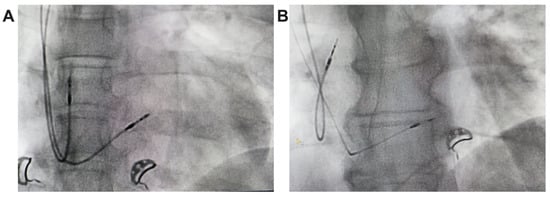

In unipolar pacing, left bundle branch area pacing (LBBAP) is characterized by a terminal r/R wave in lead V1 (Figure 2B,B’) or right bundle branch block (RBBB), accompanied by one of the following criteria for left bundle branch pacing: a short and consistent left ventricular activation time (LVAT from stimulus) below 80 ms at both high and low output in lead V6; the presence of the LBB potential; or a QRS transition during threshold testing or programmed ventricular pacing (from nonspecific LBBAP to specific LBBAP) [21]. Comparative fluoroscopic images for the two implant techniques/methods analyzed in our study are shown in Figure 3.

Figure 3. Radiological images, postero-anterior view, from the implant of a pacemaker with ventricular lead for RVP (A) and ventricular lead for LBBAP (B).